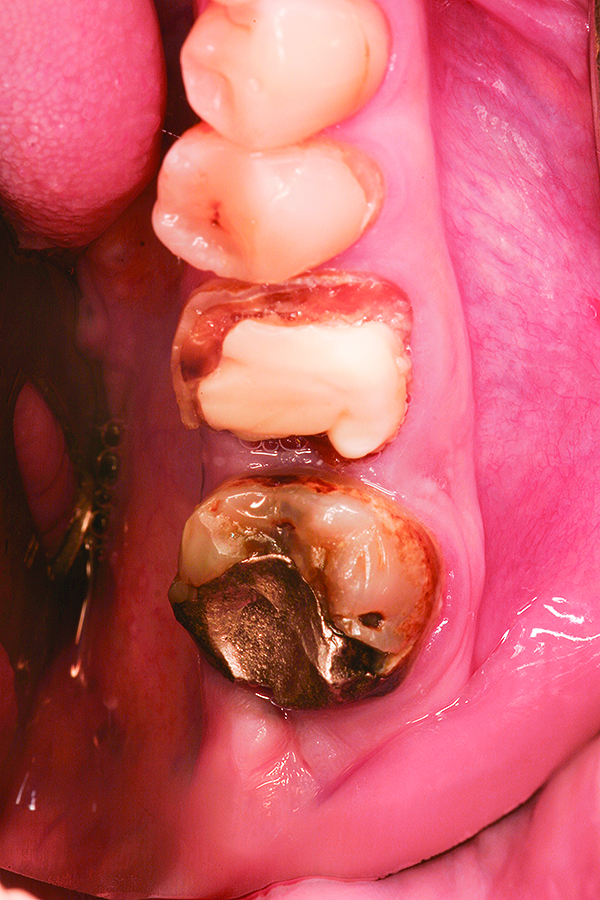

Fig 15. Case 3: Hopeless mandibular molar prior to extraction.

Figure 15

Fig 16. Note the significant dehiscence defect in the buccal wall prior to tooth extraction.

Figure 16

Fig 17. Placement of bone allograft into the extraction site.

Figure 17